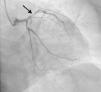

The hemodynamic team was activated and medication was begun with a loading dose of aspirin 300 mg, ticagrelor 180 mg and unfractionated heparin (5000 units). Emergency catheterization was performed (less than one hour after the onset of chest pain), which revealed a subocclusive lesion in the proximal left anterior descending (LAD) artery, severely calcified and with the appearance of a thrombus (Figure 3). A 50% ostial lesion in the intermediate branch and a <50% lesion in the mid right coronary artery were also visualized; the circumflex artery had no lesions. Primary angioplasty of the proximal LAD was performed, including thrombectomy and removal of thrombotic material, balloon predilatation and placement of a drug-eluting stent (DES) in the proximal LAD covering the origin of the first diagonal branch.